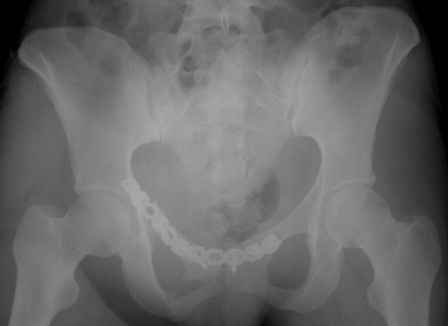

Серия до- и послеоперационных снимков этой пациентки. Хотя бы post factum обсудить. Не знаю, что можно сделать с задними отделами стержневым аппаратом, но три крепких парня открытым путем с помощью "волшебных" слов еле-еле смогли отрепонировать - сзади все было очень ригидно!